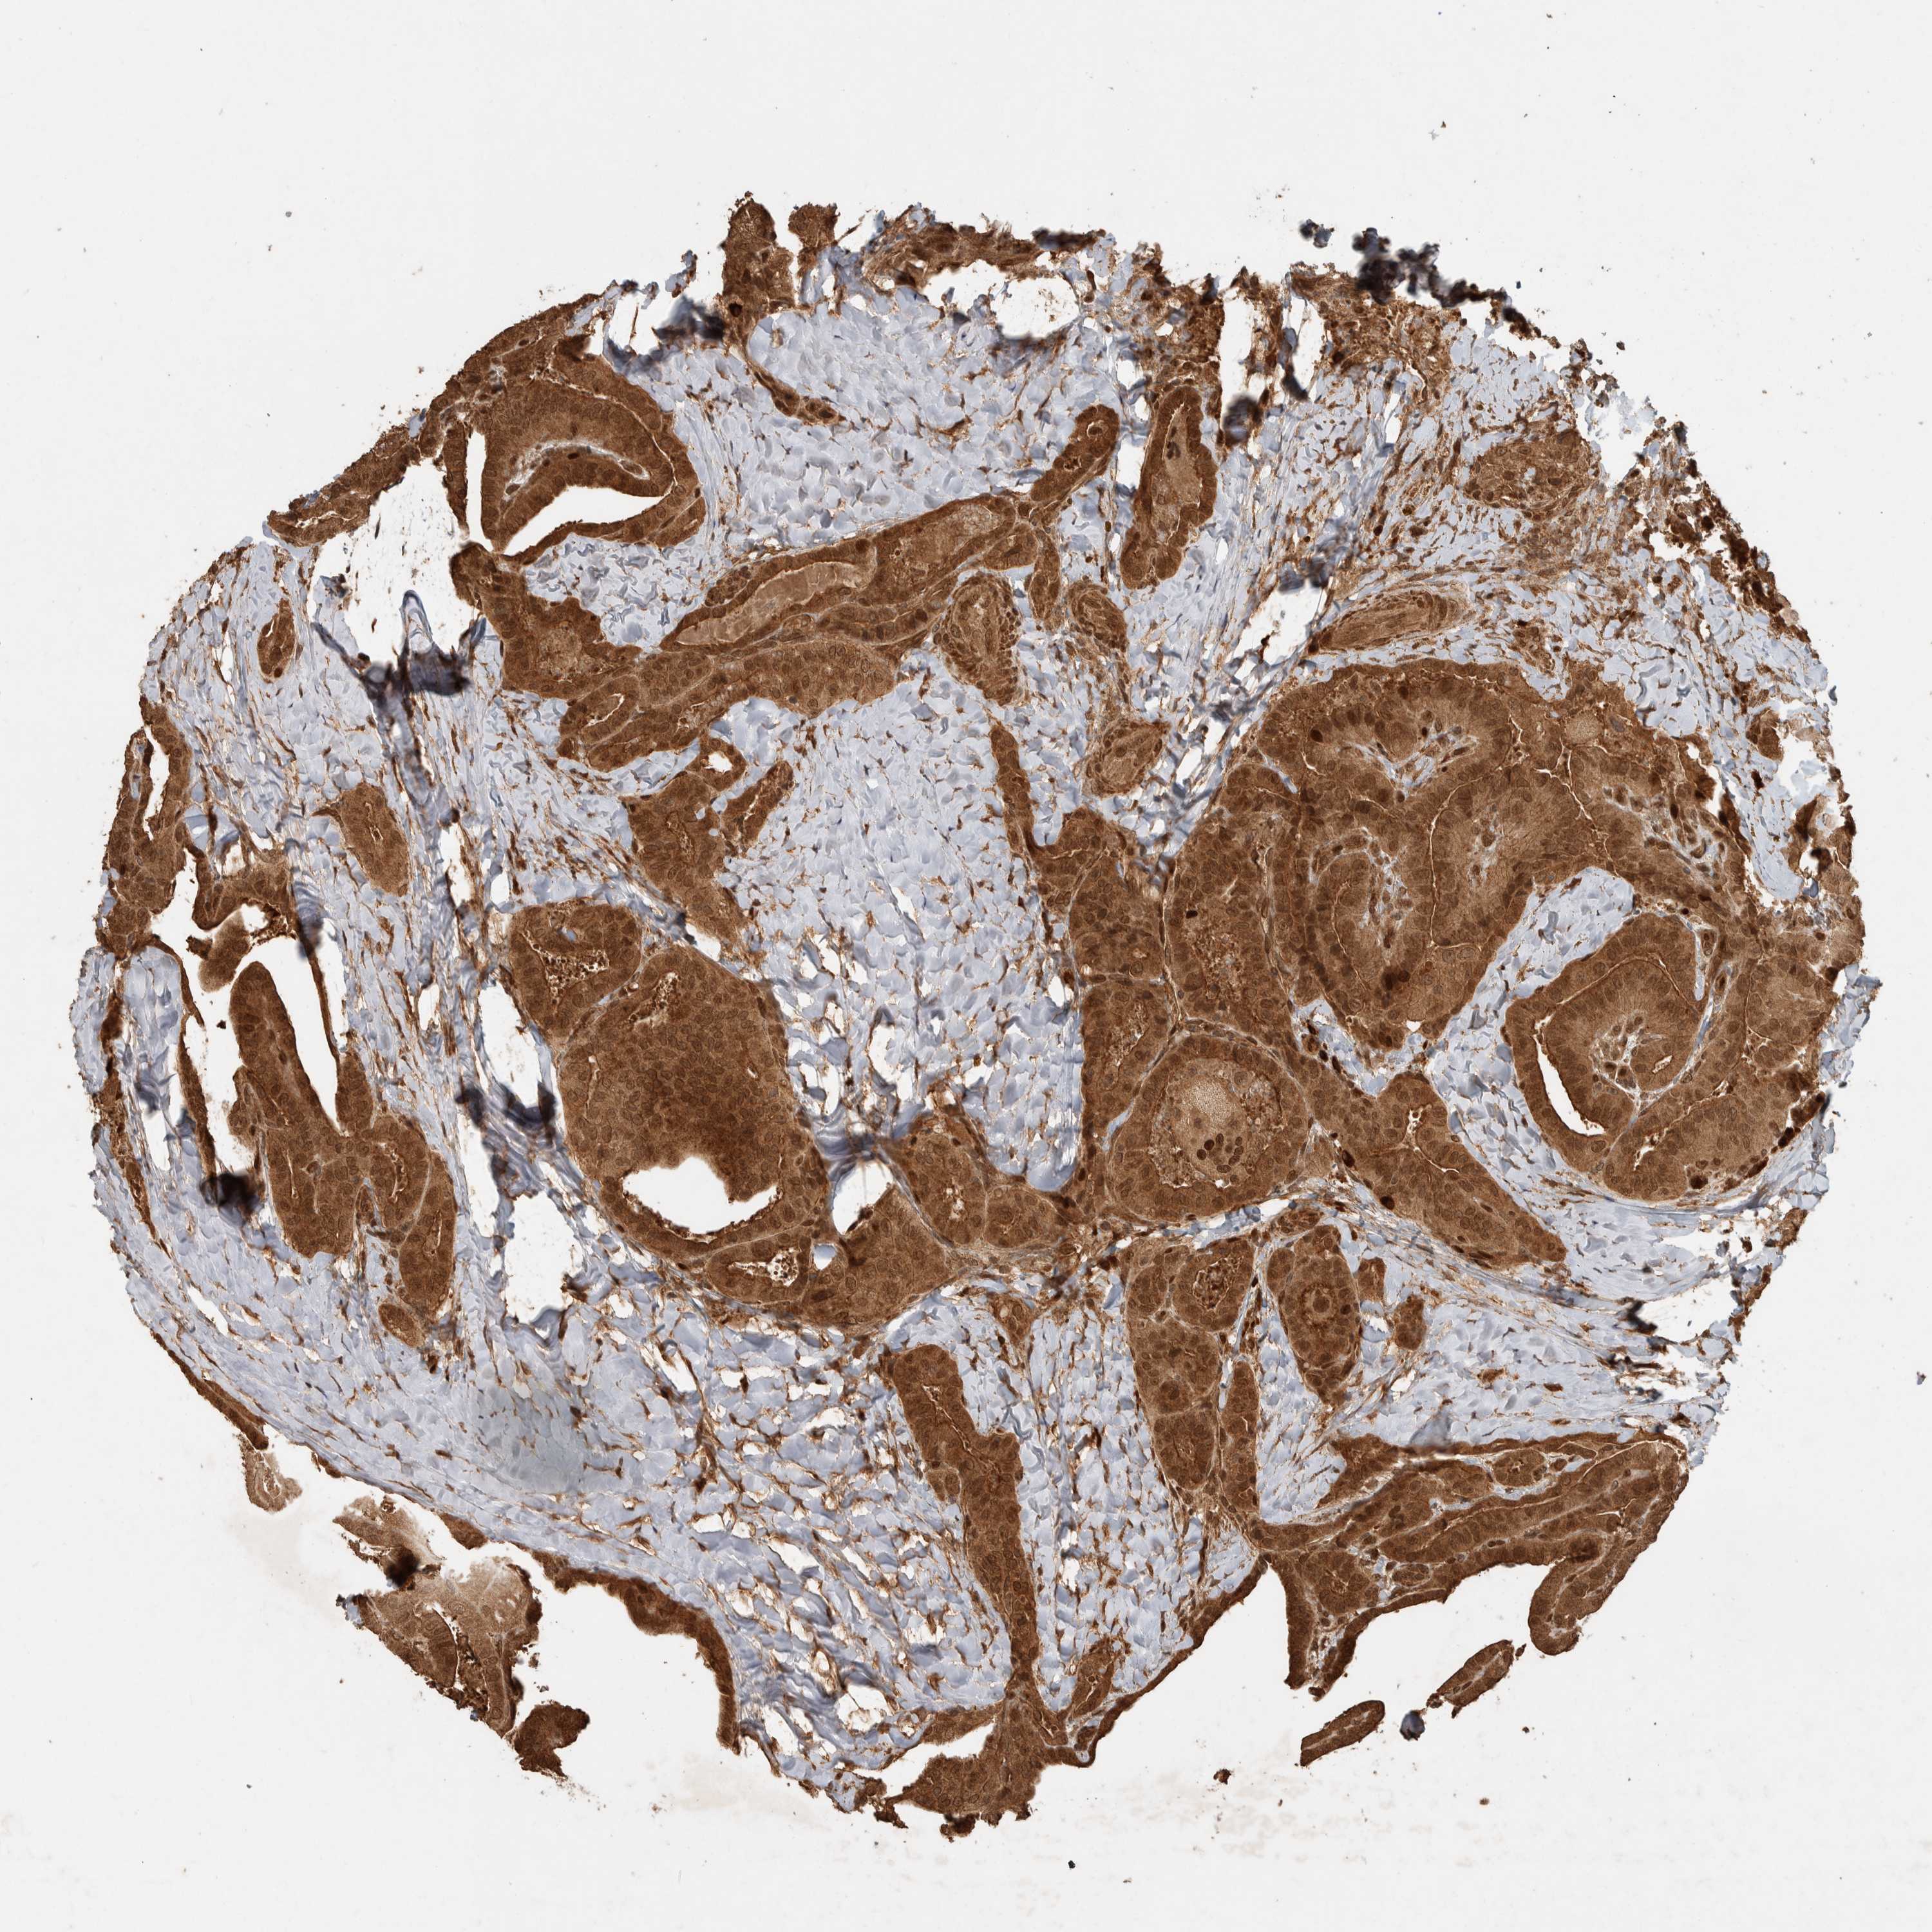

THYROID CANCER - Protein expressioni

A mouse-over function shows sample information and annotation data. Click on an image to view it in a full screen mode. Samples can be filtered based on level of antibody staining by selecting one or several of the following categories: high, medium, low and not detected. The assay and annotation is described here.

Note that samples used for immunohistochemistry by the Human Protein Atlas do not correspond to samples in the TCGA dataset.

Antibody stainingi

Antibody staining in the annotated cell types in the current human tissue is reported as not detected, low, medium, or high, based on conventional immunohistochemistry profiling in selected tissues. This score is based on the combination of the staining intensity and fraction of stained cells.

Each image is clickable and will lead to virtual microscopy that enables deeper exploration of all samples and also displays staining intensity scores, fraction scores and subcellular localization as well as patient and tissue information for each sample.

Antibody HPA023319

Antibody HPA023320

Antibody HPA023321

Antibody HPA023325

Staining

High

Medium

Low

Not detected

Intensity

Strong

Moderate

Weak

Negative

Quantity

>75%

75%-25%

<25%

None

Location

Nuclear

Cytoplasmic/membranous

Cytoplasmic/membranous,nuclear

Papillary adenocarcinoma, NOS

Follicular adenoma carcinoma, NOS